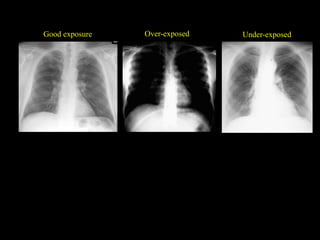

Good exposure Under-exposed

Over-exposed

Over-exposed Under-exposed